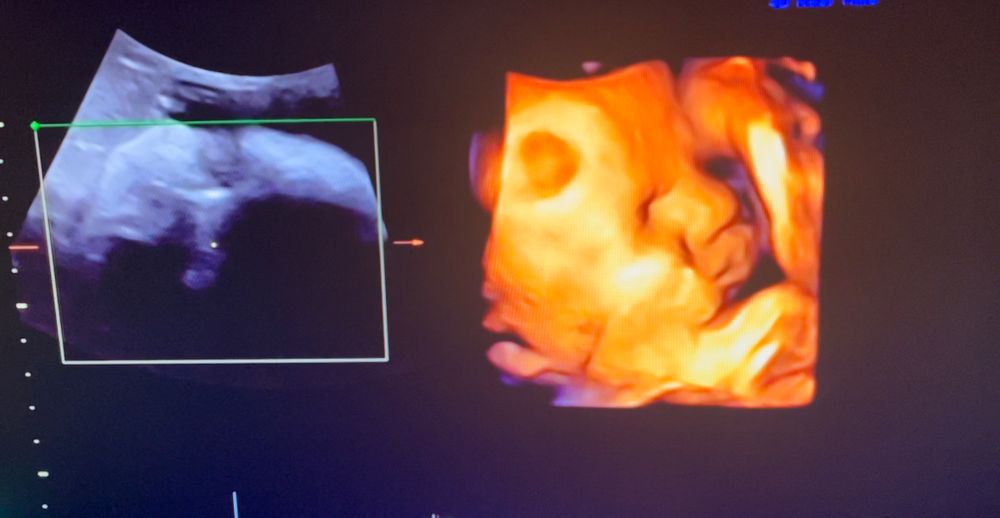

3 скрининг ✔️ 32 недели

А у меня вот плацента второй степени зрелости (сказали это норма), воды в нормальном количестве, шейка длинная, зев закрыт (по словам врача должна спокойно доходить до конца). Так что как-то так 😊